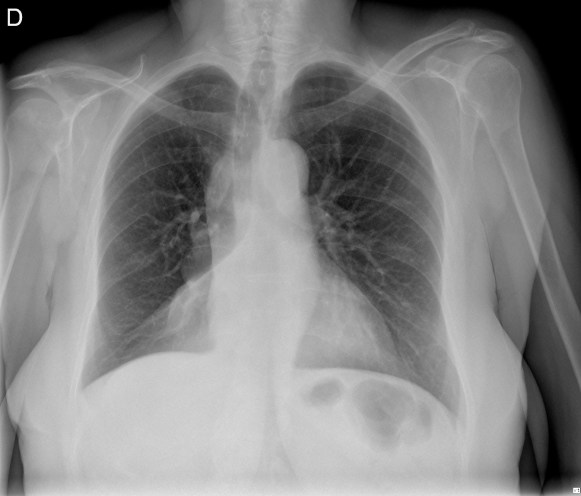

CASO: Revisión.

Hallazgos:

- Mastectomía derecha.

- Resto del estudio sin hallazgos de significación.

RECUERDA LA SISTEMÁTICA PARA NO OLVIDAR NINGUN HALLAZGO. A esta paciente le han extirpado la mama derecha, motivo por el cual se observa una asimetria entre las densidades de las bases pulmonares.